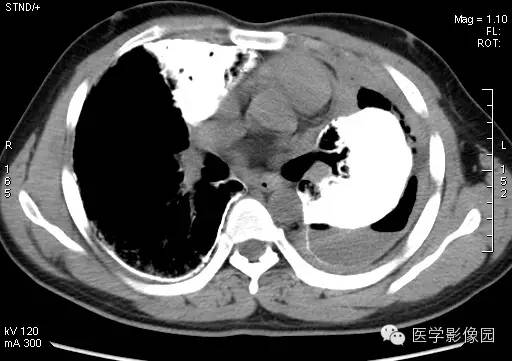

【病例】尘肺1例X线及CT影像表现

男性,36岁,镀锌工作史1年。

尘肺的主要病理改变为肺间质弥漫性纤维化及弥漫性灶周肺气肿,主要累及周围肺组织和支架结构,如肺泡壁、小叶间隔和支气管血管周围组织。